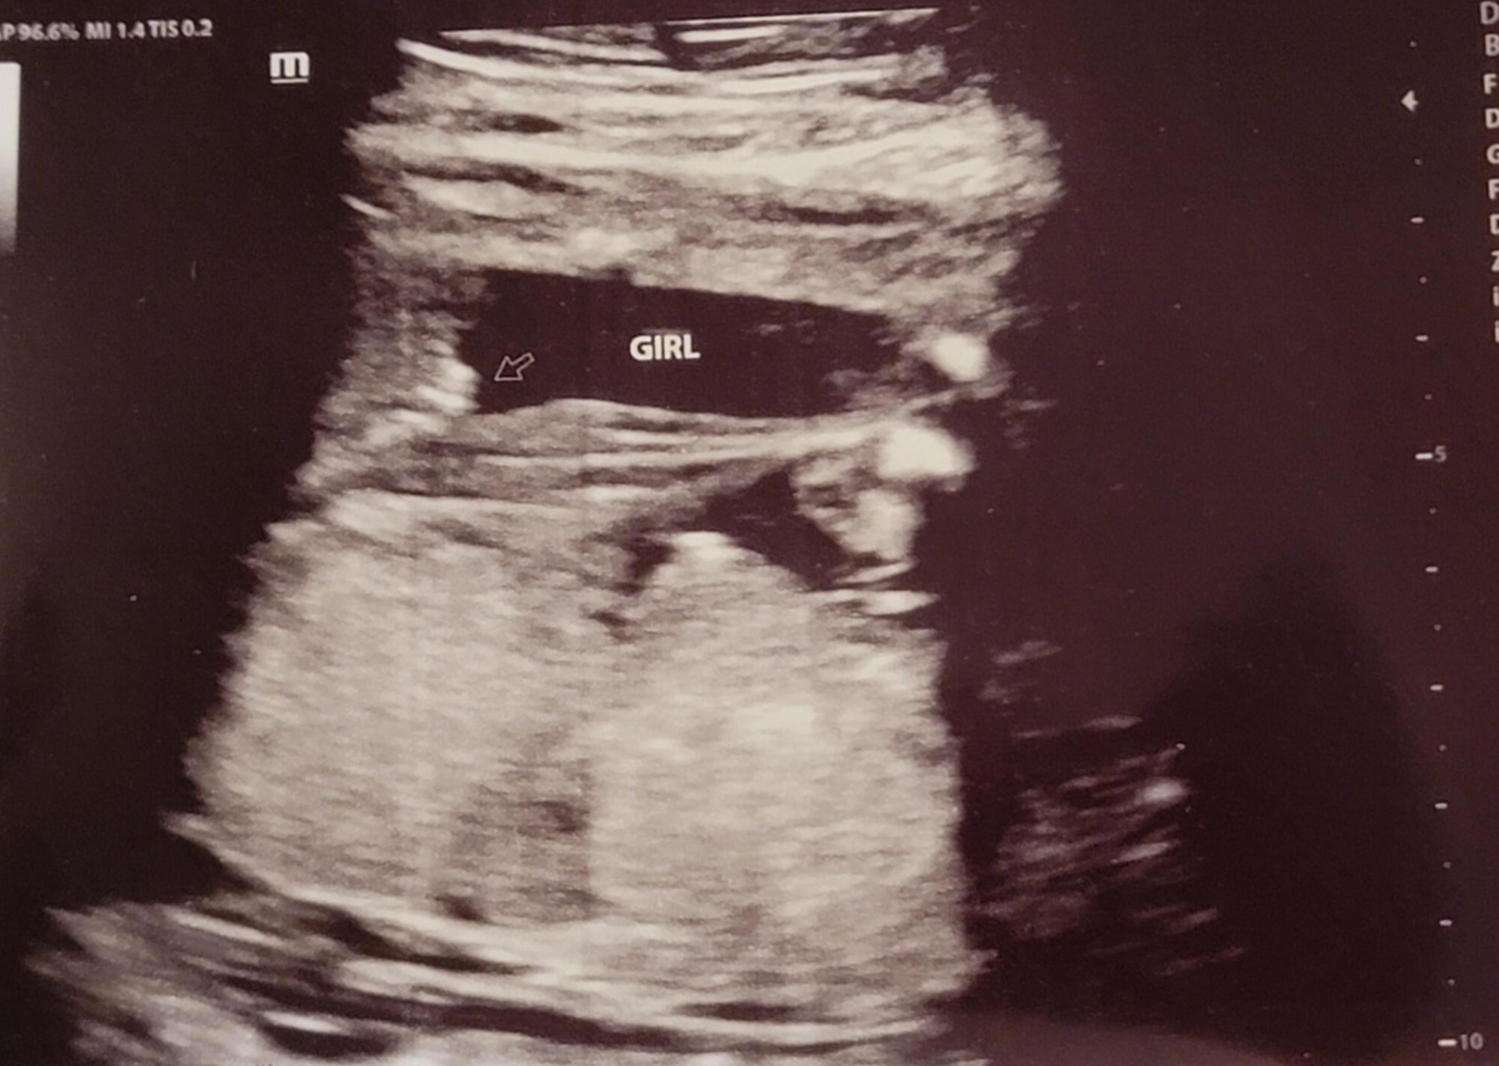

그리고 초음파 봐주시는 분께서 13주차가 되면 정확히 알 수 있으니 다음 주에 오라고 하셔서 일주일 뒤 다시 방문을 했습니다. (위에 사진은 12주 차 때 아들이라고 보여주신 초음파 사진이에요~ 화살표 보면 툭 튀어나와있는 부분을 보여주면서 아들이라고 하셨어요~)

아 진짜 전문가는 다르구나~ 이렇게 이른 주수에도 성별을 알 수가 있구나 생각을 했지만 이 시기 때는 성별을 정확히 알 수 없다는 글들을 봐서 살짝~ 의심스럽기도 했지만 그래도 100프로라니깐 ㅎㅎ 믿어보았어요~ 근데 위에 사진을 보면 성별을 알 수 있는 각도 법이 있는데 각도가 딸 같아서 긴가민가~하긴 했지만 의심은 잠시! 전문가 분을 믿기로 ㅋㅋㅋㅋ